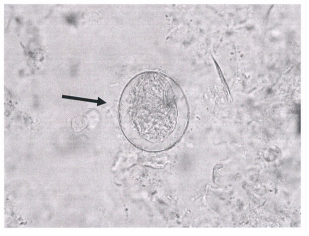

7 糞便檢體中看到如附圖的蟲卵,大小約 170×60 μm,應是下列何者的蟲卵?

(A) 埃及血吸蟲(Schistosoma haematobium) (B) 東方毛線蟲(Trichostrongylus orientalis) (C) 曼森血吸蟲(Schistosoma mansoni) (D) 薑片蟲(Fasciolopsis buski)